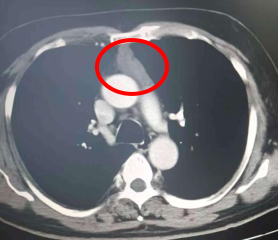

60岁的李先生(化名)近两年来深受胸闷、胸痛症状困扰,有时还出现呼吸气喘的情况,严重影响生活质量。两个月前,他慕名来到娄底市中心医院就诊,经胸部CT等详细检查后,被确诊为前纵隔肿瘤,肿瘤大小约51*19毫米。更棘手的是,该肿瘤位置较深,前方被胸骨遮挡,后方紧邻心脏、大血管等重要器官,手术操作空间狭窄,稍有不慎便可能引发严重并发症,手术难度极大。

(术前CT显示前纵隔肿瘤)